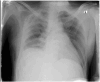

Case presentation: We present a case of 28 years old gentleman, Sudanese, with intermittent fever, non-productive cough, weight loss and night sweats. Chest X-ray then CT chest revealed a large right pleural collection invading the chest wall. Chest tube was inserted, fluid analysis was taken, and a bronchoscopy was done. A diagnosis of Empyema Necessitans was confirmed and patient was started on anti-TB regimen with clinical improvement.